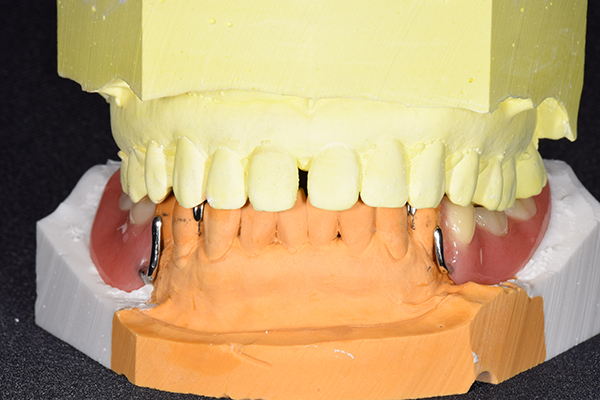

ケース2(自費の総入れ歯と部分入れ歯)

上下の入れ歯が外れやすくなったということでいらっしゃいました。 顎の骨はしっかりしていましたので、精密な型取りさえすればしっかりした入れ歯がつくれると思いました。 また下には6本歯が残っていましたが、虫歯になっている歯もありました。 かぶせ物のなかで大きな虫歯があった歯があり、1本だけ残せない状態でした。

上の入れ歯は確かに吸着は甘くなっていました。 また下の入れ歯はバネの一部が壊れており、安定感がなくなっていました。

精密な型取りの後、噛み合わせのチェックをしていきました。 かぶせ物も同時に作っていきました。

歯を並べた後、かぶせ物のフレーム作ってもらいました。先に歯を並べて理想の位置を決めておくことが大切です。

完成した入れ歯とかぶせ物です。 入れ歯への寛容度が高い患者様でしたので、 金属は使用せず、プラスチックのみで上は仕上げました。 下顎も歯は1本減ってしまいましたが、しっかり 入れ歯が維持できる様な構造にしました。

お口の中に入れた状態です。 見た目も最初とほとんど変わることなく作成できました。 維持や吸着に関しても問題ないようでした。

年齢 80歳・女性

主訴 上下の入れ歯が外れやすくなった

治療期間 3ヶ月

治療費 .メタルボンドクラウン:550,000円

.義歯:990,000円(税込、上下)

治療方針 長年使ってきた義歯の人工歯が磨耗し、臼歯部での咬合がすくなくなり、入れ歯の安定も悪くなり、あたりどころが悪くなって痛みが出ている。 そのため、入れ歯を上下作りかえる必要がある。

治療内容 過去に治療を行ったことのある歯が再度虫歯になってしまっているところがあり、すでに残せない状態にまでなっていたため、歯を一本抜歯した。 その後、かぶせ物と入れ歯を同時に作成していった。

特記事項 歯を抜いた後は、2〜3ヶ月歯ぐきの回復を待ってから入れ歯を作るため、待機期間があります。その間、古い入れ歯を調整しながらそのまま使うか、新し物をつくっておく必要があります。ただし、入れ歯は保険治療で作成する場合、6ヶ月は新しいものが作れないという決まりがあるので保険で全て作りたい場合は注意が必要です。